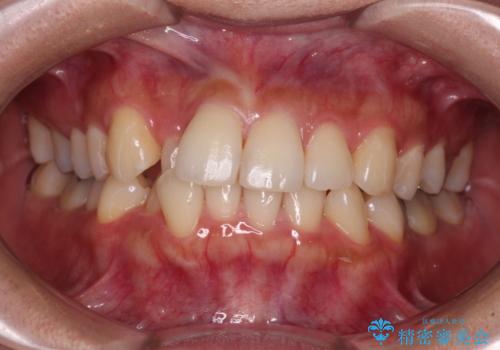

- 前歯のデコボコと前方に斜めに飛び出した前歯を気にして来院された患者様です。

口元の突出感はあまり気になっていませんでしたが、上下の前歯の前後差が大きかったため、上顎左右の第一小臼歯を抜歯し、上顎が裏側装置であるハーフリンガルにて矯正治療を行うこととしました。

咬合力が非常に強く、スペースがなかなか閉じなかったことと、上下の正中が著しくずれてきてしまったため、下顎左側小臼歯を途中抜歯することとなりました。

歯の動きが鈍く、矯正治療だけで4年以上の期間を要することとなりました。

矯正治療後は、気になっていた銀歯を全てセラミックとし、きれいな口元に仕上げることができました。